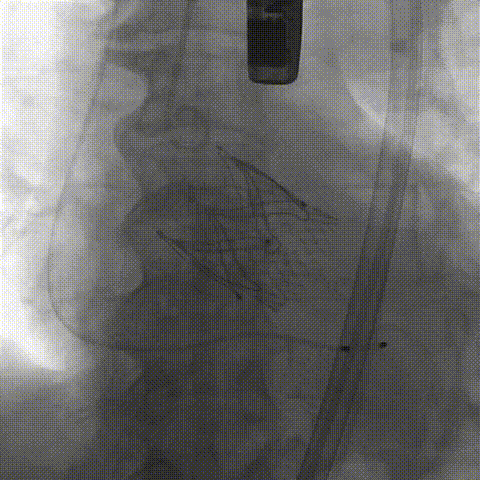

2026年伊始,TaurusTrio经导管主动脉瓣系统在复旦大学附属中山医院,浙江大学医学院附属第二医院,中国医学科学院阜外医院,首都医科大学附属北京安贞医院,四川大学华西医院等多家临床中心成功开展上市后全国首批植入。这不仅是TaurusTrio正式走向广泛临床应用的重要里程碑,更标志着中国单纯主动脉瓣反流介入治疗正式迈入了“心键合璧”的全新纪元。